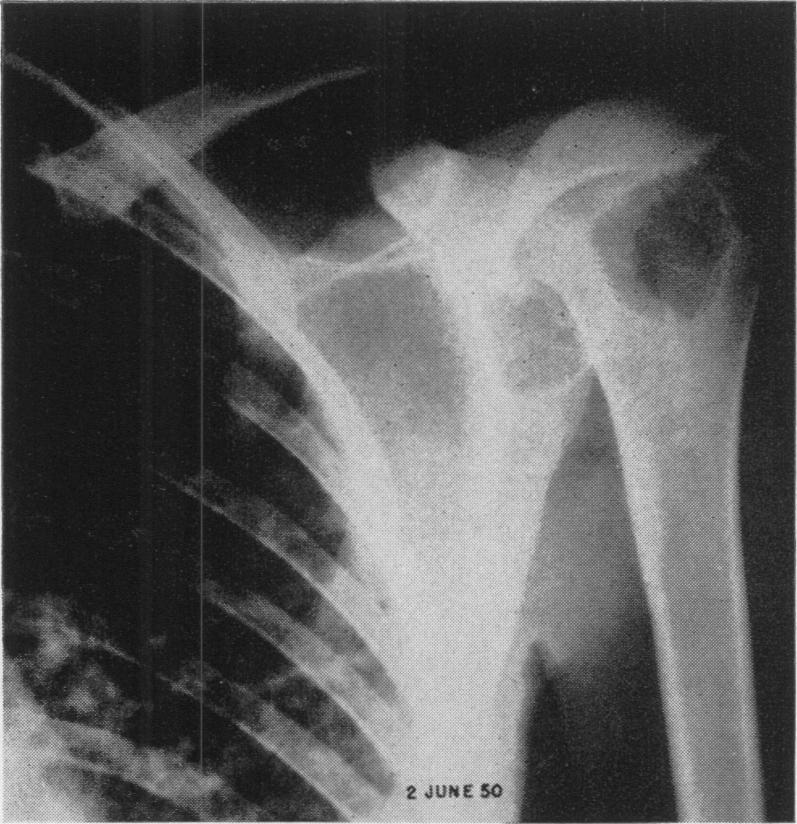

FORSEE J H, BLAKE H A

Ann Surg. 1954 Jan;139(1):76-83. doi: 10.1097/00000658-195401000-00009.